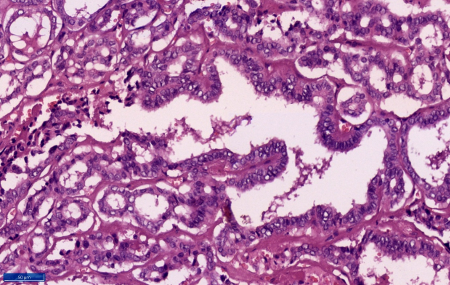

consistency. At microscopy sections showed a duct

made up of fibrous wall with extensive calcific

areas. The lumen of the duct showed a tumor

comprising of cells in predominantly papillary

pattern along with occasional follicle formations.

Individual cells lining the papillae and the

follicles showed crowding and overlapping. These

tumour cells demonstrated moderate eosinophilic

cytoplasm, mild nucleomegaly, round to oval with a

single nucleus showing nuclear clearing,

margination of the chromatin and occasional intra

nuclear grooves. Scanty mitosis were also noted.

The wall of the duct shows normal thyroid

follicles and chronic inflammation. The tumour

cells were embedded in the duct walls at places.

However, tumour cells were not extending beyond

the duct. (Figure 3-6) Hence a final diagnosis of

papillary carcinoma of thyroid-classic type (PTC),

arising in a thyroglossal duct cyst was made.

Figure

6: Section shows tumoral papillae line by

tumour cell showing nuclear crowding,

overlapping, nuclear clearing and

grooving. (Haematoxylin and Eosin, x 400) |